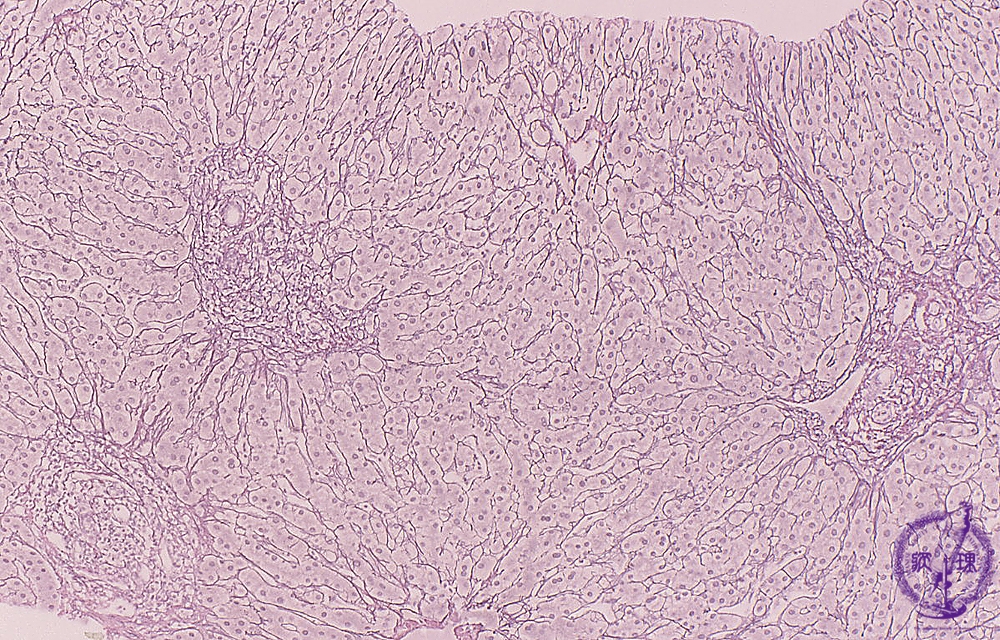

Microscopic image (silver stain, intermediate-power): There is portal fibrous expansion (red box) with varying degrees of bridging fibrosis (blue line).